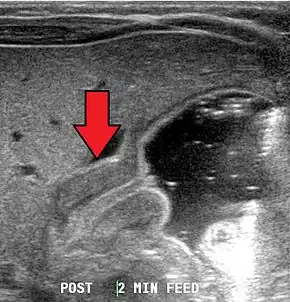

Most cases of pyloric stenosis are diagnosed/confirmed with ultrasound, if available, showing the thickened pylorus and non-passage of gastric contents into the proximal duodenum. Muscle wall thickness 3 millimeters (mm) or greater and pyloric channel length of 15 mm or greater are considered abnormal in infants younger than 30 days. Gastric contents should not be seen passing through the pylorus because if it does, pyloric stenosis should be excluded and other differential diagnoses such as pylorospasm should be considered. The positions of superior mesenteric artery and superior mesenteric vein should be noted because altered positions of the these two vessels would be suggestive of intestinal malrotation instead of pyloric stenosis.[8]